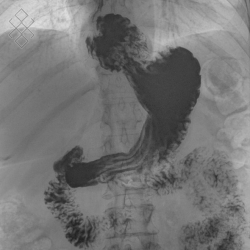

Transit Oeso-Gastro-Duodénal (TOGD)

Vous boirez un liquide de contraste qui vous sera donné par le manipulateur en radiologie. Avant l'examen, un anti-spasmodique peut aussi vous être injecté en intraveineux.

L'examen du transit oeso-gastro-duodénal peut engendrer des selles blanches s'il s'agit d'un contraste baryté.